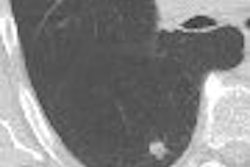

Multislice cardiac CT angiography (CTA) offers a fast, comprehensive, one-stop look at the heart that could potentially replace invasive coronary angiography for many applications.

The benefits of cardiac CTA are potentially "revolutionary," said Dr. Guy Weigold, a cardiology faculty member and director of cardiac CT at the Washington Hospital Center in Washington, DC. But it's important to remember that CTA is tricky scan, a "one-shot acquisition with a relatively thin margin of error and limited forgiveness," he said. "Patient selection and preparation clearly are key to obtaining diagnostic images on a consistent basis."